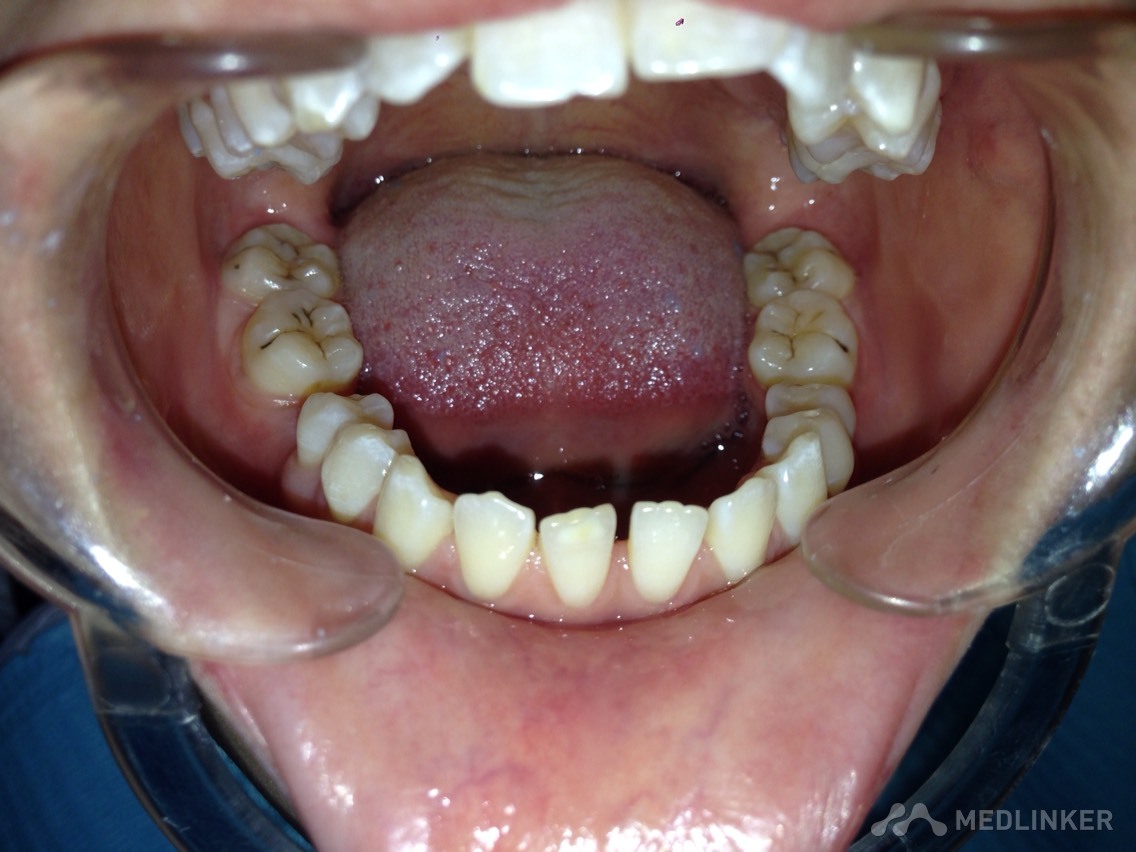

患者女,23岁,想做隐形无托槽矫正

上颌前牙牙列拥挤,下颌前牙散在间隙,下颌双侧第一磨牙缺失多年,开合